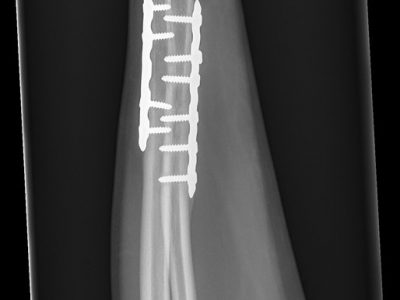

Παρακάτω παρατίθενται ακτινογραφίες καταγμάτων του άνω άκρου που αντιμετωπίζονται με εσωτερική οστεοσύνθεση ή επανορθωτική χειρουργική με αρθροπλαστική.